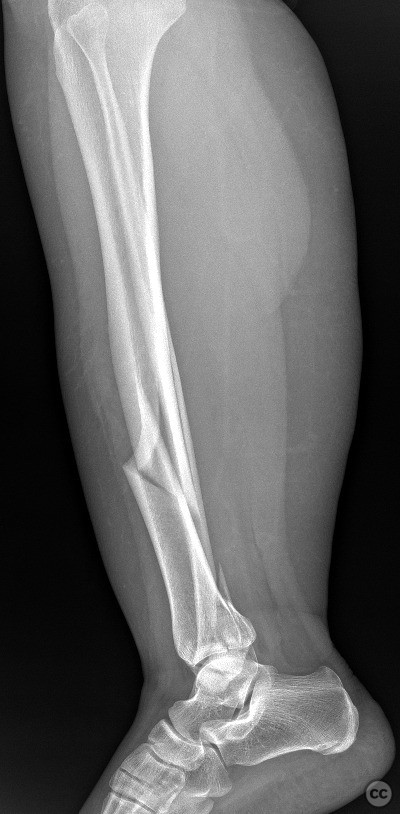

Diaphyseal - AO/OTA 42x

Tibia - AO/OTA 4x

Fibula - AO/OTA 4Fx

Dec 08 2025

By Seçkin Doğan

Ipsilateral Tibial Shaft and Trimalleola...

türkiye, Turkey